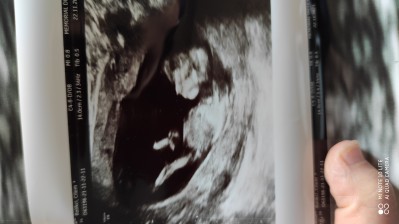

12haftalik gebelik cinsiyet tahmini nedir sizce

Gebelik haftası 12

Etti canım kız dedi ama emin değilim dedi

Ay ne güzel net çıkmış masallah erkek barız ortada cinsiyeti netlesince tekrar yazın lütfen

Kizlar cinsiyeti belli oldu inşallah bı prensesim olacak (◍•ᴗ•◍)❤